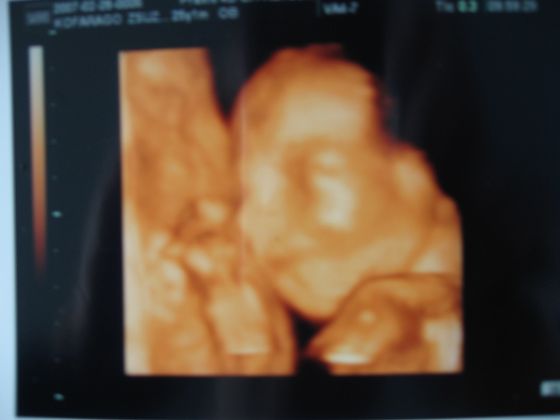

Tegnap Kata megírta, hogy a lánykának kinőtt a kukaca, így fiúcskánk lesz. Ha nem gond rakok róla egy képet. Éppen mosolyog, és a méhfalat simizi.